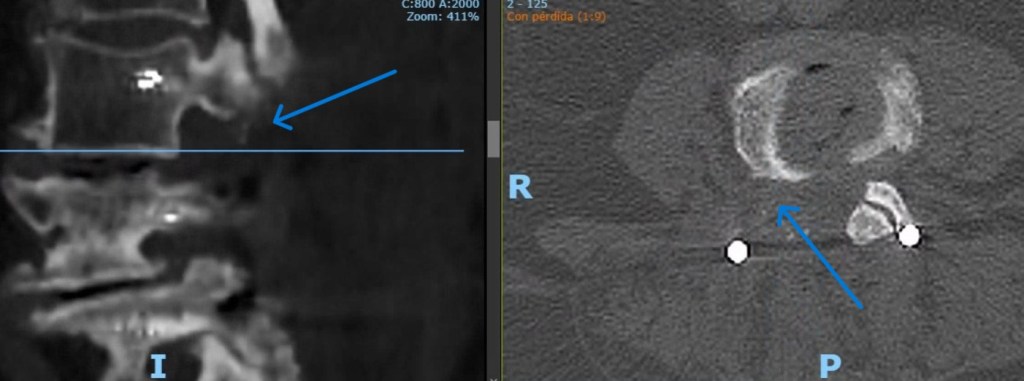

Patología traumática de la columna vertebral: Está representada por las fracturas vertebrales. Este fenomeno cada vez más frecuente debido a la alta prevalencia de la osteoporosis va a dar lugar a la ruptura de los elementos óseos que conforman las vértebras, a veces motivada por traumatismos menores, lo que además de dolor importante puede generar fenómenos de inestabilidad y/o lesiones neurológicas debidas a la compresión de la médula espinal o las raíces nerviosas.

–Fracturas vertebrales: Frecuentes sobre todo en la columna dorso-lumbar, pueden aparecer como consecuencia de mecanismos muy diversos; desde grandes traumatismos, en cuyo caso su tratamiento puede estar condicionado por la presencia de otras lesiones, o bien tras traumatismos banales o incluso de forma espontánea, sin traumatismo alguno. Estos últimos casos definen las «fracturas patológicas» en las que es preciso buscar una causa subyacente estructural o sistémica que haya provocado el debilitamiento óseo. Esta situación es especialmente frecuente en mujeres tras la menopausia debido al desarrollo de osteoporosis. Estos casos precisan iniciar un tratamiento para compensar la desmineralizacón ósea. El tratamiento de las fracturas depende fundamentalmente del grado de deformidad asociado, la afectación de ligamentos (ambos aspectos definen la presencia o no de inestabilidad) y el que exista o no una lesión neurológica. En caso de fracturas estables sin déficit neurológico se emplea una ortesis mientras que en presencia de inestabilidad o afectación neurológica debe valorarse la cirugía.

- Estabilizacion vertebral percutánea: Es el procedimiento empleado para tratar los casos que precisan fijar dos o más vértebras debido a la presencia de inestabilidad o fracturas. Gracias al empleo de imagen intraoperatoria y a los sistemas de fijación de alta precisión es posible llevar a cabo esta técnica de forma mínimanente invasiva mediante pequeñas incisiones de apenas 2 cm a través de las cuales se introducen tornillos al pedículo de la vértebra así como barras laterales. El respeto por la musculatura paraespinal, clave para el resultado final, es por tanto máximo gracias a esta técnica. La ejecución de la misma gracias al aprovechamiento de aspectos como la colocación bicortical de los implantes y las técnicas de reduccion percutánea de la deformidad permiten un restablecimiento de la anatomía en una amplia proporción de casos con un riesgo mínimo.